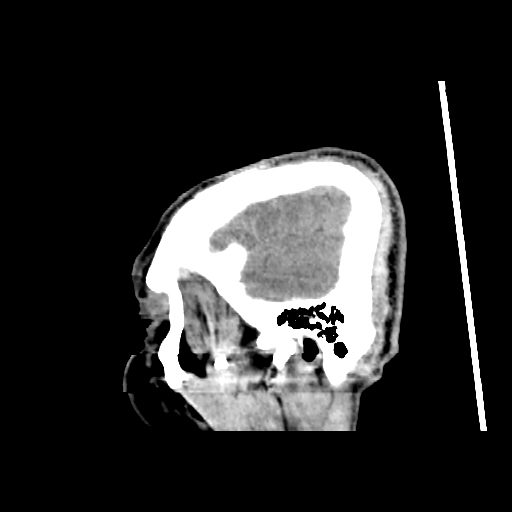

A 60 years old man with seizure since 12 years

Plan CT scan was done on 22 march 2016